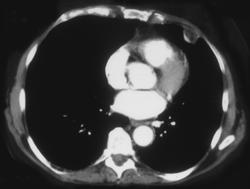

Thickened Trachea Due to Rhinoscleroma